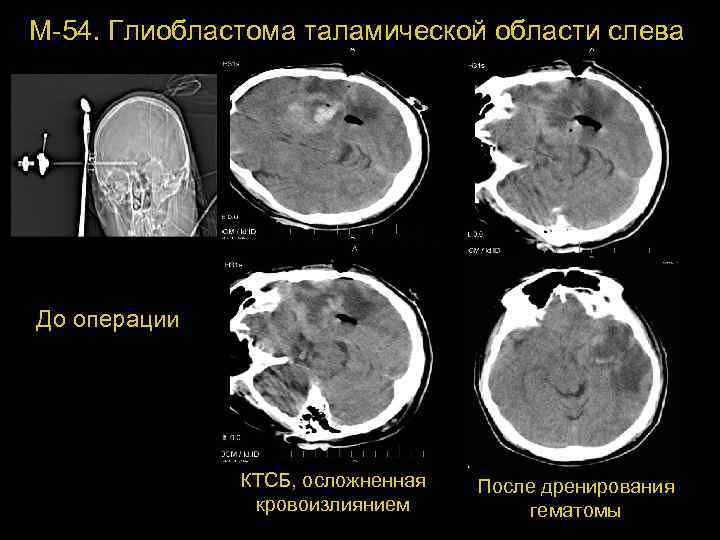

М-54. Глиобластома таламической области слева До операции КТСБ, осложненная кровоизлиянием После дренирования 73 гематомы